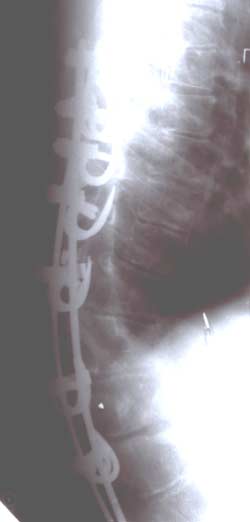

История создания устройства для

оперативного лечения сколиотической

деформации началась в 70-е годы. А.А.

Гайдуков и Л.Л. Роднянский предложили

динамическую конструкцию эндокорректора.

Она представляла собой пластины уложенные

вдоль позвоночника на вершине деформации

и фиксированные проволокой к дужкам

или остистым отросткам позвонков на

нескольких уровнях. Но данная конструкция

не оправдала надежд авторов и была

оставлена.

|

В дальнейшем

А.А. Гайдуков разработал и создал

эндокорректор с деротационными скобами

с фиксацией в блоках креплений на

нескольких уровнях. Данный эндокорректор

позволил эффективно на 60-100% корригировать

деформацию при сколиозе III-IV степени.

Но тяжелая многочасовая операция,

травматичность вмешательства, проволочная

фиксация и нередкие неврологические

осложнения ограничивали применение

данной методики.